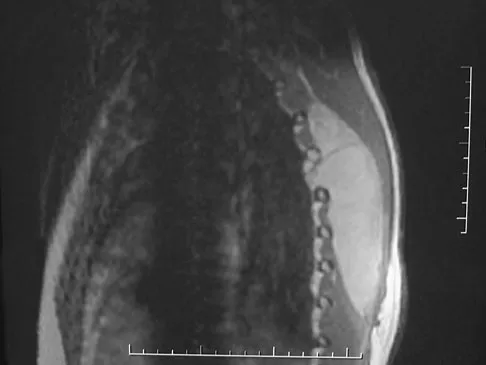

A 24-year-old professional football player underwent surgery for a symptomatic cervical disk herniation with radiculopathy 9 months ago. A current radiograph is shown in Figure 17. He has normal neurologic findings, no pain, and full range of motion. A CT scan shows a solid fusion. When can he expect to return to play?

Correct Answer: Immediately

The radiograph shows that the two-level anterior cervical diskectomy and fusion has healed. In addition, the patient has good range of motion and the neurologic examination is normal. Based on these findings, the patient can return to play immediately. Patients with one- or two-level anterior cervical diskectomies and fusions that have healed fully can return to play. Any loss of motion, persistent neurologic deficit, or significant adjacent segment degeneration may preclude a player from returning. Thomas B, McCullen GM, Yuan HA: Cervical spine injuries in football players. J Am Acad Orthop Surg 1999;7:338-347.